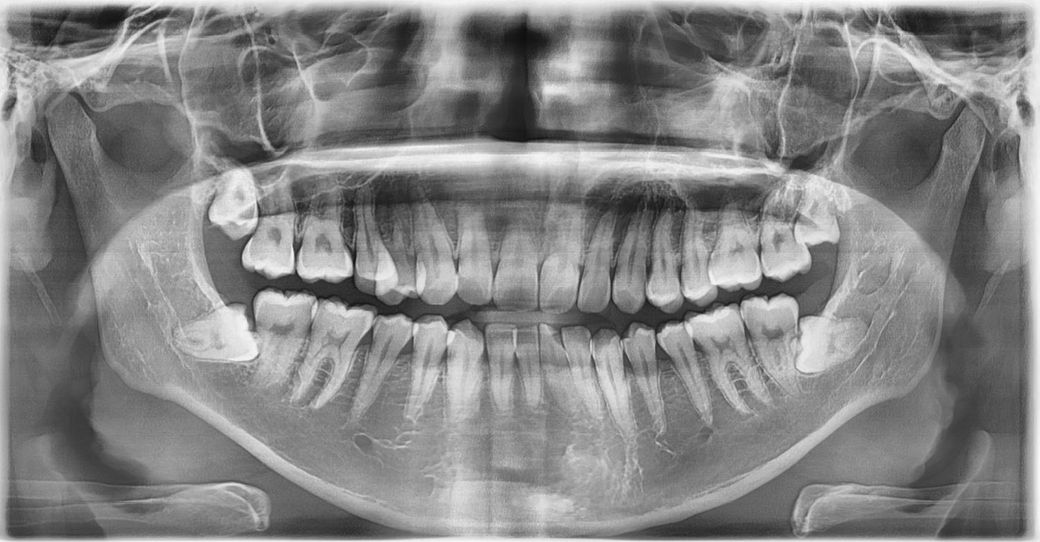

위쪽 사랑니부터 발치를 할까 하는데 꼭 발치를 해야 할 상황인가요? 아님 좀 더 상황을 지켜보다 뽑아도 되는지 궁금합니다!

현재 사랑니가 큰 문제는 아니지만 추후에 문제를 일으킬 가능성은 높아보여 빼는 게 좋겠습니다.

사랑니가 완전히 매복되어 있다면 발치를 할 필요는 없습니다. 하지만 사랑니가 부분적으로 나와있거나 해서 주변조직에 문제를 발생시킬수 있다면 발치를 해주는 것이 좋습니다.

지금 당장 아프거나 불편한게 아니라면 일단 조금 더 지켜보셔도 되겠습니다만 맹출 방향이나 위치가 사진상으로 보기에는 앞에 있는 어금니의 충치를 유발하거나 잇몸염증을 유발하기 쉬운 상태라 뽑아주시는 것도 좋겠습니다. 젊었을땐 뼈가 탄성도 좋고 치유도 잘되기 때문입니다.

전반적으로 사랑니가 옆 어금니에 영향을 줄 가능성도 있고, 위생관리도 어려운 양상이긴 합니다 발치가 아주 급하고 그러진 않으나 빼면 좋을것 같습니다